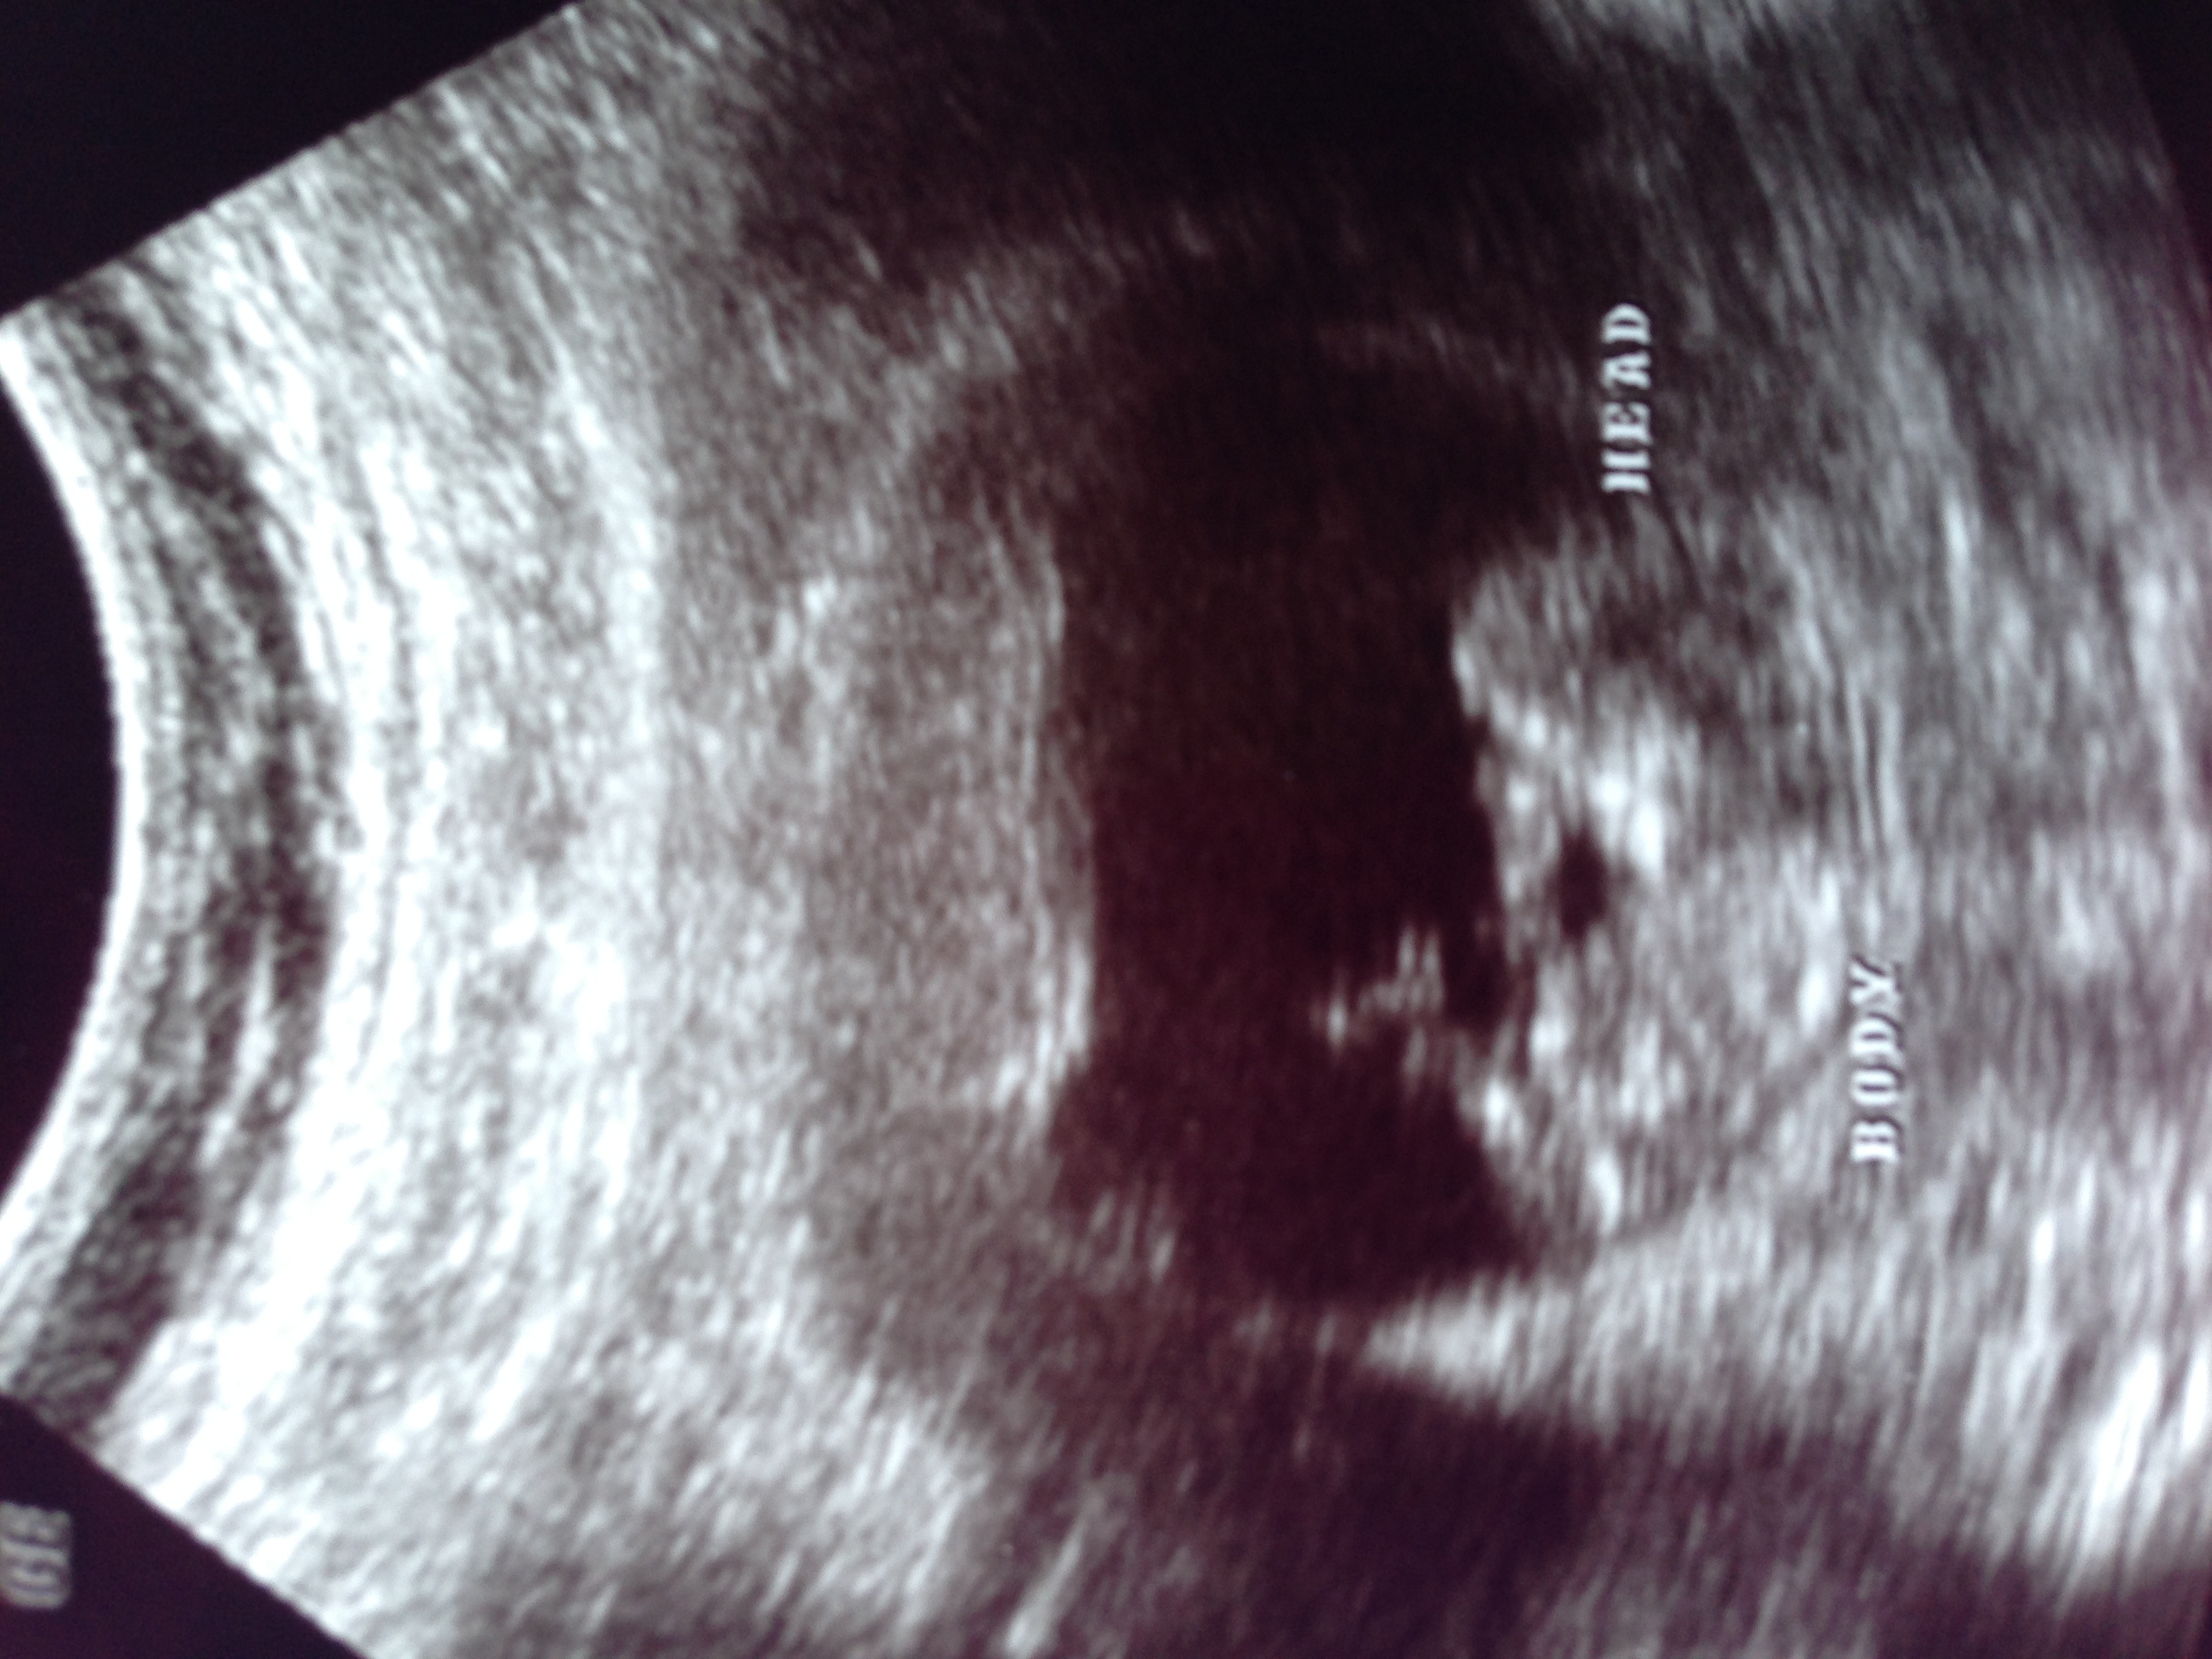

No longer a blob it is a baby!!

11wks 2 days! So excited!!

ETA: the picture didn't post

image.jpg